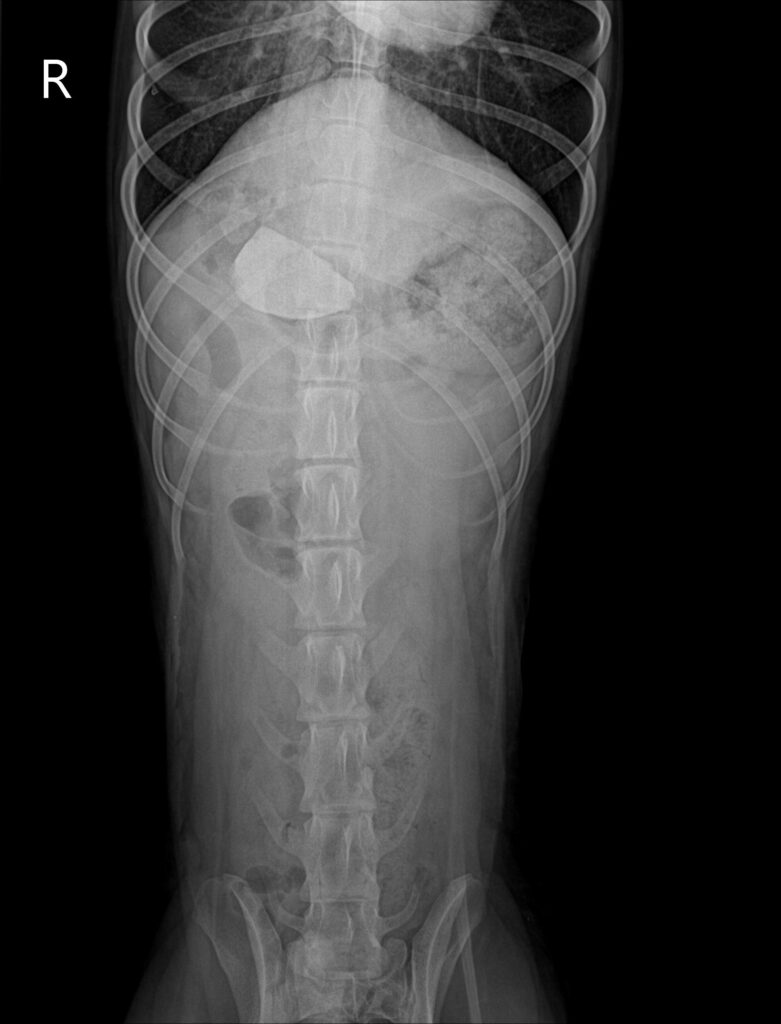

수술 전 방사선 사진 / 출처: 미래동물의료센터

엑스레이 검사에서 위 내부에 밝은 음영의 물질이 확인되었으며, 형태와 밀도로 보아 돌 이물로 강하게 의심되는 소견이었습니다.이물의 크기와 위치상 자연 배출이나 구토 유도만으로는 제거가 어렵다고 판단되어 위절개 수술을 통한 이물 제거가 필요하다고 설명드렸습니다.